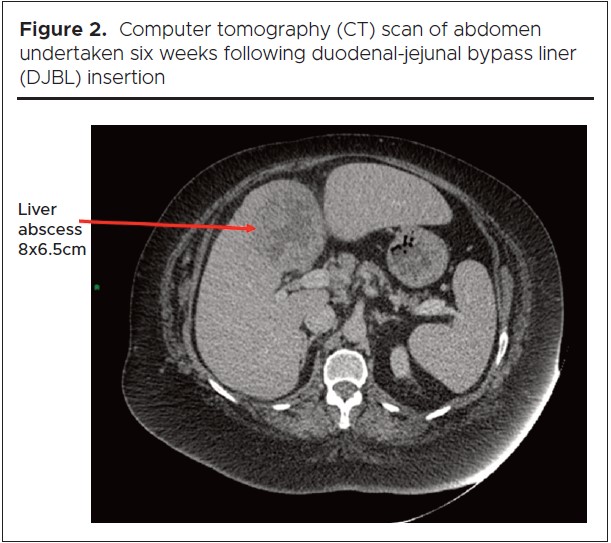

This patient presented six weeks following DJBL insertion in July 2014 with nausea, upper abdominal pain and fever; her C-reactive protein (CRP) was 232 mg/L (reference range 0 – 10), her white blood cell count (WCC) was normal. She was found to have an 8.0 x 6.5 cm abscess in the left hepatic lobe on CT imaging (Figure 2). It was not amenable to ultrasound-guided drainage as blood vessels running anterior to the liver made the abscess difficult to access.